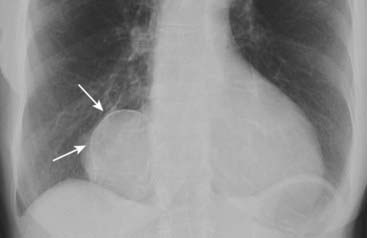

Figure 16-1 Calcified pericardial cyst.

There is a rimlike calcification (solid white arrows) that identifies the structure containing the calcification as cystic or saccular. The calcification is in the right cardiophrenic angle, an ideal location for pericardial cysts. Pericardial cysts are usually asymptomatic and discovered when a chest radiograph is obtained for another reason.